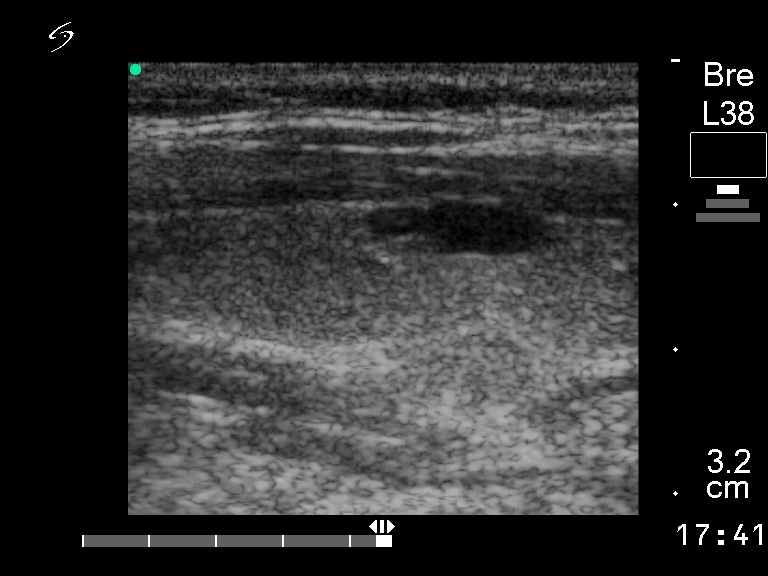

Other edifying cases - Case 7: Identifying a vessel in unusual localization within the thyroid |

Clinical presentation: a 48-year-old woman with a "nodule" discovered on sonographic screening was referred for an evaluation.

Ultrasonography: normal thyroids with a vessel in unusual location within the thyroid.

Final report: the thyroid is healthy.